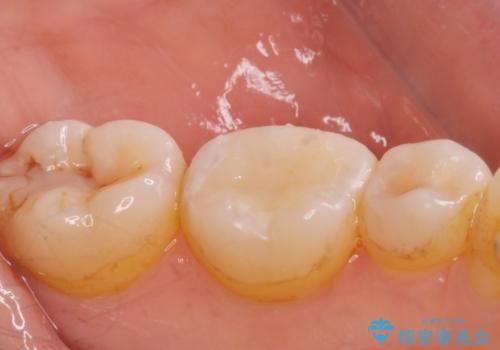

e-maxインレー治療

- 過去に治療した銀の詰め物が取れて来院された患者様です。

詰め物のやりかえをするのなら白い詰め物でやりかえたいとのことなのでe-maxインレーでの治療を行いました。

白い詰め物が入り患者様に満足してもらいました。